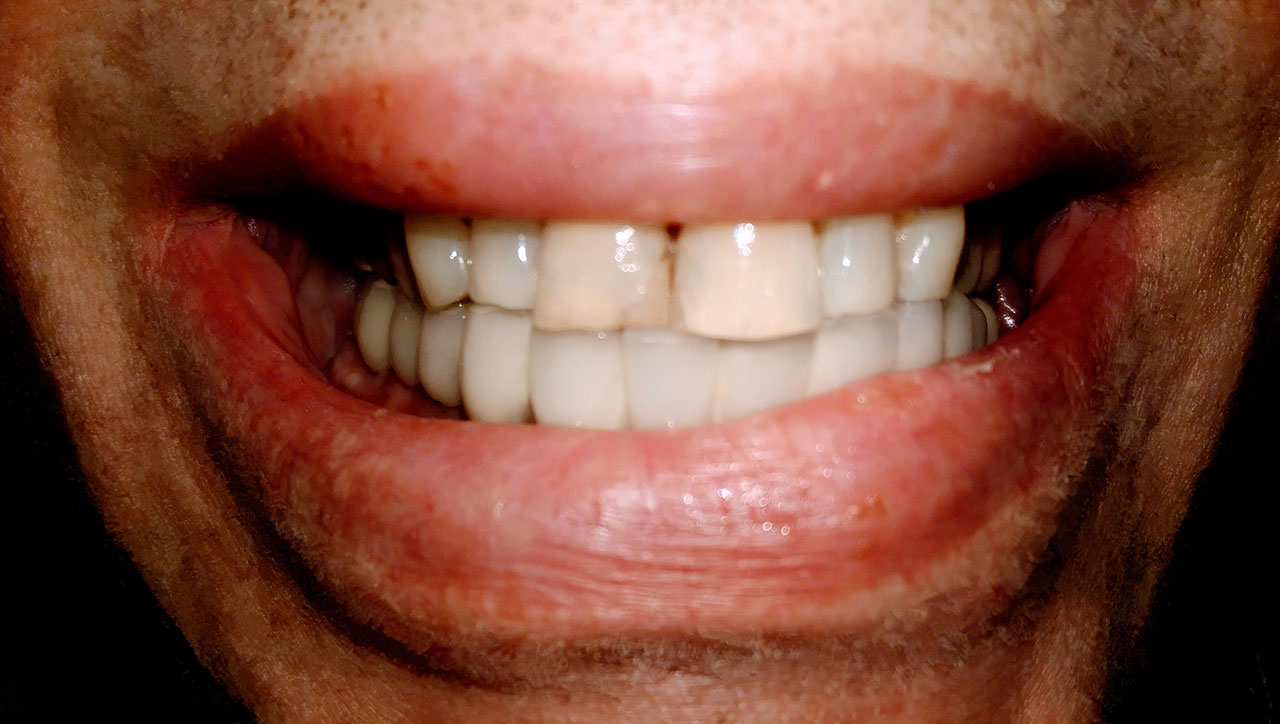

Alsó állcsont teljes rehabilitációja 72 óra alatt

Alsó állcsont teljes rehabilitációja 72 óra alatt, azonnal terhelhető implantátumokkal súlyos paradontitisben szenvedő dohányzó páciens esetében. Az alsó állcsont fogai mind mozogtak az előrehaladott fogágypusztulás miatt.

A fogakat eltávolítottuk, a gyulladt, fertőzött csontot kitakarítottuk, kifertőtlenítettük, majd azonnal implantáltunk.

Svájci, IHDE márkájú, azonnal terhelhető implantátumokat helyzetünk be, és ezekre harmadnapra rögzített, hosszútávú, fémvázas, esztétikus műanyaggal leplezett hidat ragasztottunk be.

Ezt az ideiglenes hidat a sebek gyógyulása miatt használjuk, de tartóssága miatt véglegesként is használható. A legtöbb esetben, ahogy itt is, 6 hónap múlva porcelán hídra cseréljük, a teljes gyógyulás után.